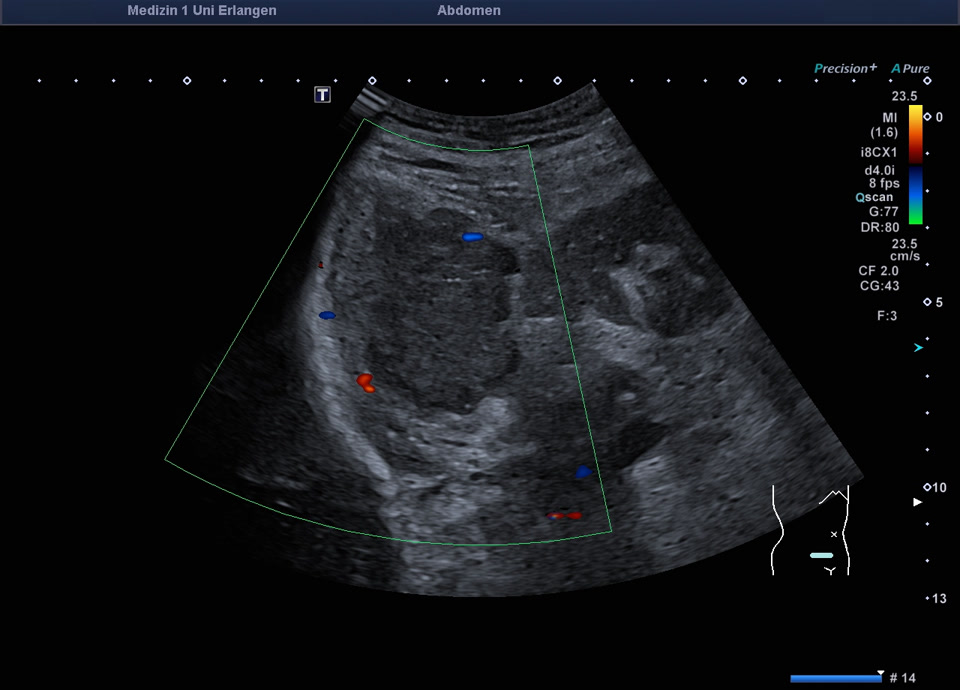

Retroperitoneum

• Psoas metastasis of urothelial carcinoma (color Doppler)

• Psoas metastasis of urothelial carcinoma